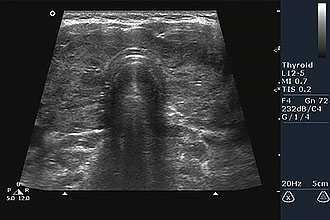

На сегодняшний день ультразвуковое исследование относится к наиболее востребованных ввиду безболезненности, безвредности, высокой информативности и простоте проведения. УЗИ горла и гортани широко используется в отоларингологии, онкологии, эндокринологии, пульмонологии и других медицинских специализациях.

При исследовании щитовидной железы врач может визуализировать неоднородные очаги, дополнительные образования (узлы, кисты), уменьшение/увеличение размеров железы. При необходимости диагностика осуществляется в посттравматическом периоде для определения тяжести поражения, выявления месторасположения инородных тел.

При исследовании железистой ткани щитовидки врач акцентирует внимание на консистенцию и плотность, которая отображается на экране зонами различной плотности.

Ультразвуковая диагностика в области шеи широко применяется и активно изучается при острой воспалительно-гнойной патологии (паратонзиллярные абсцессы, флегмоны), при патологии гортани и трахеи, слюнных и щитовидных желез, а также при метастазировании злокачественных новообразований в лимфатические узлы.